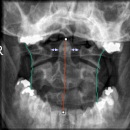

Dens (Spezialaufnahme)

CAVE

- 1) Exakte Aufnahmetechnik? - Projektion korrekt?

- 2) Atlantoaxialer Übergang: Distanz Dens-Massa lateralis ? (Distanz 3-5mm = V.a. parteielle Ruptur des Lig transversum; Distanz > 5mm = V.a. komplette Ruptur des Lig. transversum)

- 3) Konturlinien überprüft: Laterale Konturlinien, Dornfortsatzlinien

Beurteilung von

- Atlas

- Axis mit Dens axis

- Atlantoaxialgelenk

Einteilung der Densfraktur nach Anderson und D`Alonso

- Typ 1: Fraktur des oberen Anteils des Dens (stabile Fraktur!)

- Typ 2: Densbasis-Querfraktur (instabile Fraktru!)

- Typ 3: Densbasisfraktur mit Ausdehnung auf den Axiskörper (stabile Fraktur!)

- CAVE: Os odontoideum

Einteilung der Atlasfraktur

- Typ 1: Vordere Atlasbogenfraktur

- Typ 2: Hintere Atlasbogenfraktur

- Typ 3: Vordere und hintere Atlasbogenfraktur (Jeffersonfraktur)

- Typ 4: Fraktur der Massa lateralis

- Typ 5: Proc. transversus Fraktur